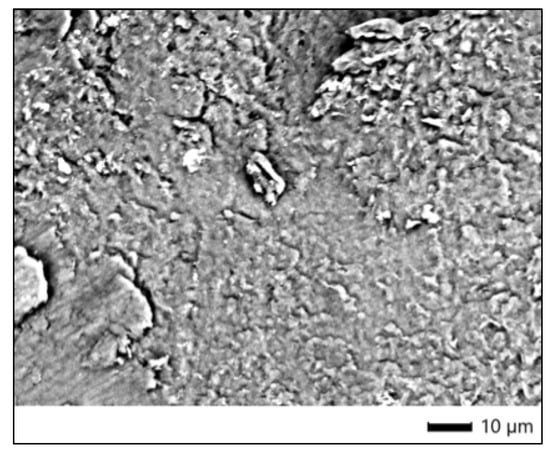

3.7. SEM Analysis—Bleached Samples

The enamel surface of the specimen treated with Opalescence Boost (sample 6P) showed notable alterations in surface morphology compared to the control. At ×1100 magnification, the SEM image revealed a relatively smooth surface with parallel polishing lines, but with the presence of dispersed surface deposits and granular accumulations. These deposits appeared clustered along abrasively modified areas and presented a more heterogeneous surface texture. Although no deep cracks or widespread erosive defects were visible, the enamel displayed signs of superficial restructuring, suggesting mild surface interaction with the 40% hydrogen peroxide bleaching agent used in this protocol (Figure 4).

3.8. EDS Analysis—Bleached Samples

Elemental composition assessed by EDS in four analyzed regions (Spc_001–Spc_004) indicated the following trends:

• Oxygen (O): Present at high atomic percentages (33.24–45.62%), oxygen remains the dominant element, reflecting the preserved inorganic matrix of the enamel.

• Calcium (Ca): Ranged from 13.80% to 27.94% (atomic), indicating variability in mineral content. Slight reductions in some areas may suggest early-stage demineralization.

• Phosphorus (P): Detected at 7.32–14.65% atomic, supporting the presence of calcium phosphate compounds, though some fluctuation between points was observed.

• Carbon (C): Present in moderate levels (15.51–25.17%), possibly reflecting organic residue or surface contamination; one of the values was noticeably lower than in the control.

• Sodium (Na): Found in trace amounts (0.50–1.06%), consistent with enamel’s natural composition.

• Magnesium (Mg): Ranged from 0.33% to 7.41% atomic, with a marked increase at one point (Spc_004), which may indicate local chemical imbalance or residual bleaching components.

• Aluminum (Al) and Silicon (Si): Detected in minor quantities only in Spc_002 and Spc_004, possibly from sample handling or polishing residue.

• Chlorine (Cl): Found in low concentrations (0.25–0.32%), potentially originating from bleaching by-products or residual preparation materials.

These findings indicate that Opalescence Boost, while not causing severe mineral loss, may induce localized compositional changes and surface modification, visible both morphologically and chemically. The overall enamel structure remains largely intact, although variations in Ca and P levels suggest some interaction with the bleaching agent.